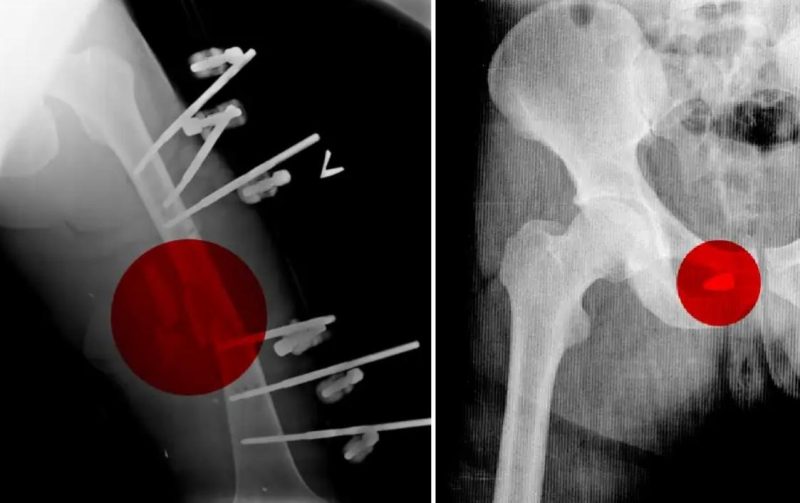

Тем не менее Андрею удалось тайно сделать копии рентгеновских снимков десятков военнослужащих, проходивших лечение в Мозырской городской больнице. На сканах были указаны имена и возраст солдат, многим из которых было от 19 до 21 года.

У одних отсутствовали глаза, другим требовалась ампутация. Прибыли с гангренозными, раздробленными конечностями, некоторые были парализованы, один потерял часть мозга, другой — нижнюю челюсть. Рентгеновские снимки показали, что некоторые из них были перевязаны жгутами в течение нескольких дней, чтобы остановить кровь.

Как пишет CNN, Андрей в конце марта был задержан по обвинению в коррупции [вероятно, речь идет о так называемом «деле ортопедов»], из СИЗО его отпустили в мае, а в августе он нелегально покинул Беларусь. Сейчас медик вместе с семьей находится в одной из европейских стран. Для подтверждения своих слов он предоставил копии рентгеновских снимков проходивших лечение в его больнице российских солдат.

«Генерал-майор России Сергей Нырков, получивший тяжелое ранение в живот в Чернобыле, также лечился в Мозырской больнице, судя по его рентгеновскому снимку, который был среди тех, что Андрей вывез контрабандой», — пишет CNN.